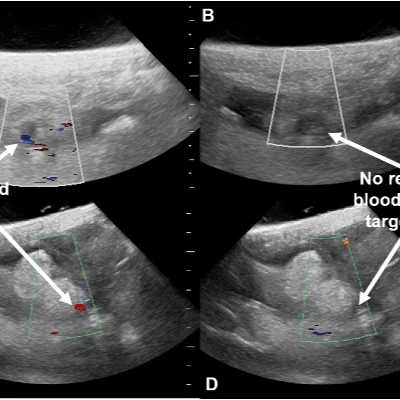

Doppler Ultrasound

Doppler studies assess blood flow in arteries and veins, helping detect

Deep vein thrombosis (DVT)

Peripheral artery disease

Carotid artery narrowing

Placental blood flow in pregnancy

These scans are crucial for vascular health and prenatal monitoring, offering dynamic insights into circulation.